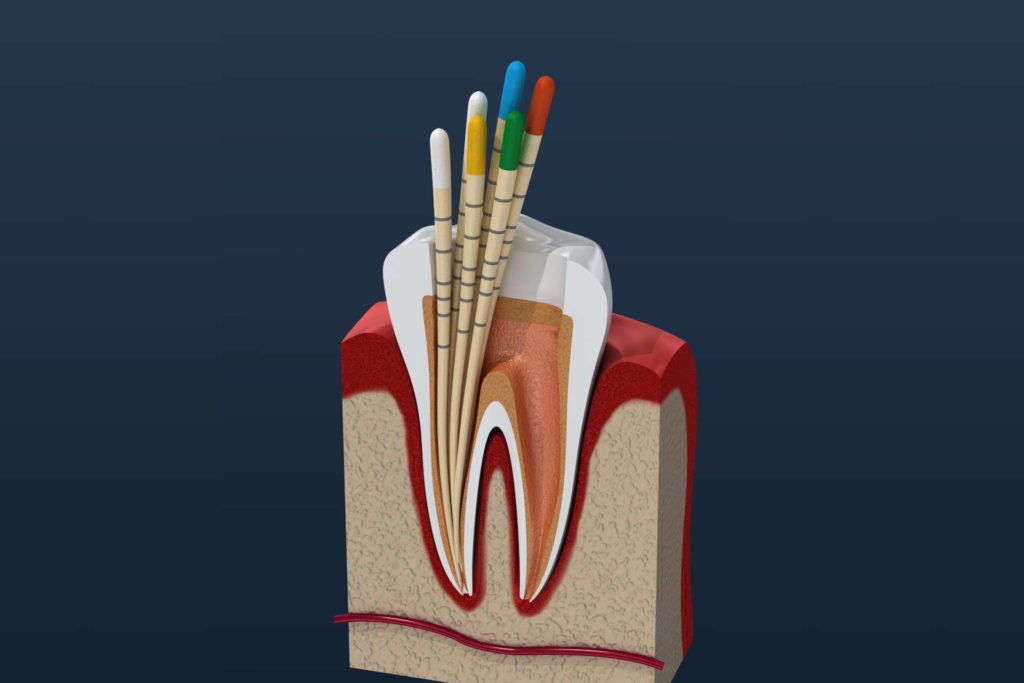

Root Canal

When tooth decay reaches the innermost dental pulp, it may cause pain and requires a root canal treatment.